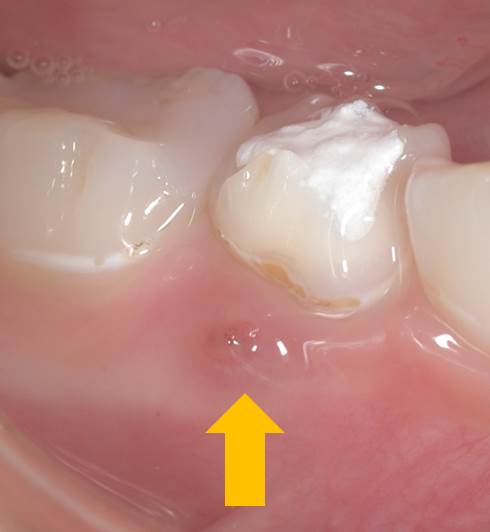

6歳の男の子です。

矢印部分に歯肉から膿瘍形成が観察されます。

歯肉から膿が出ていれば歯周病ではないかと思われますが、根管(歯の中の神経や血管が入っていて部分)の中の感染により生じています。また、年齢から歯周炎(歯周病が進み骨吸収が起こった状態)は考えられません。